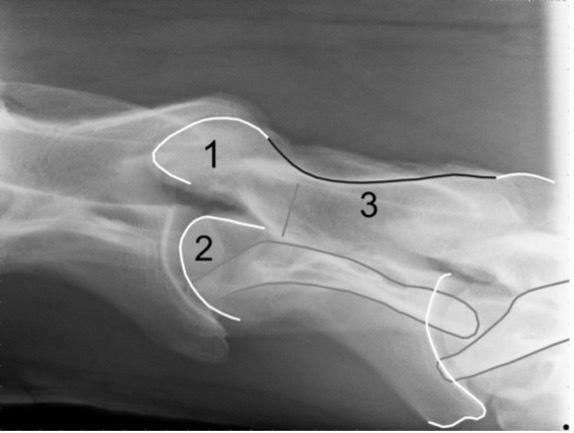

1 - cranial facet

2- cranial body

3 - lamina-pedicle junction